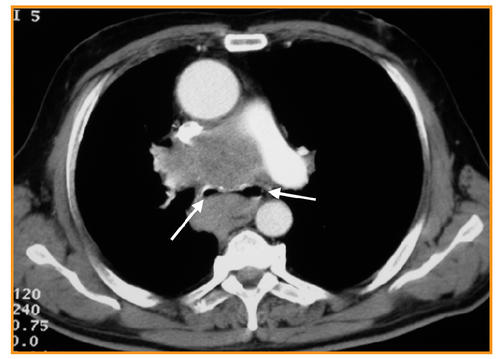

Imagerie des pathologies thoraciques chez le patient VIH ... Cette revue illustre les atteintes thoraciques infectieuses et non infectieuses chez le patient VIH au stade SIDA (moins de 200 CD4/mm 3) à l'ère des traitements antirétroviraux.Les différentes pathologies infectieuses opportunistes, tumorales et vasculaires observées chez le patient VIH ont une fréquence variable selon le degré d'immunosuppression et l'observance de la ...

Pneumopathie febrile mots fléchés. Pneumopathie organisée au sirolimus : un diagnostic à ... La pneumopathie au sirolimus, entité connue, peut se présenter sous différentes formes : apparition aiguë ou subaiguë. Elle reste un diagnostic d'exclusion. Dans notre cas, la symptomatologie principale était une altération majeure de l'état général associée à une pneumopathie unilatérale avec syndrome inflammatoire. (Pdf) Prise En Charge Radiologique Des Appendicites Aiguës ... appendicolithe (Fig. 1). Figure 1: Coupe longitudinale échographique d'un. appendice augmenté de d iamètre, à paroi épaissie, contenant du liquide et des stercolithes (flèches); en. rapport ... (PDF) Imagerie des pathologies thoraciques chez le patient ... a b Fig. 2 : Pneumopathie à Klebsiella Pneumoniae diagnostiquée en endoscopie bronchique chez un patient de 33 ans au stade sida en rupture de traitement antirétroviral (7 CD4/mm3). a Scanner thoracique montrant de multiples nodules flous, mal limités et confluents des sommets, associés à des plages de verre dépoli. (PDF) Atteintes cardiaques au cours des hyperéosinophilies ... Atteintes cardiaques au cours des hyperéosinophilies : une présentation clinique et échocardiographique polymorphe